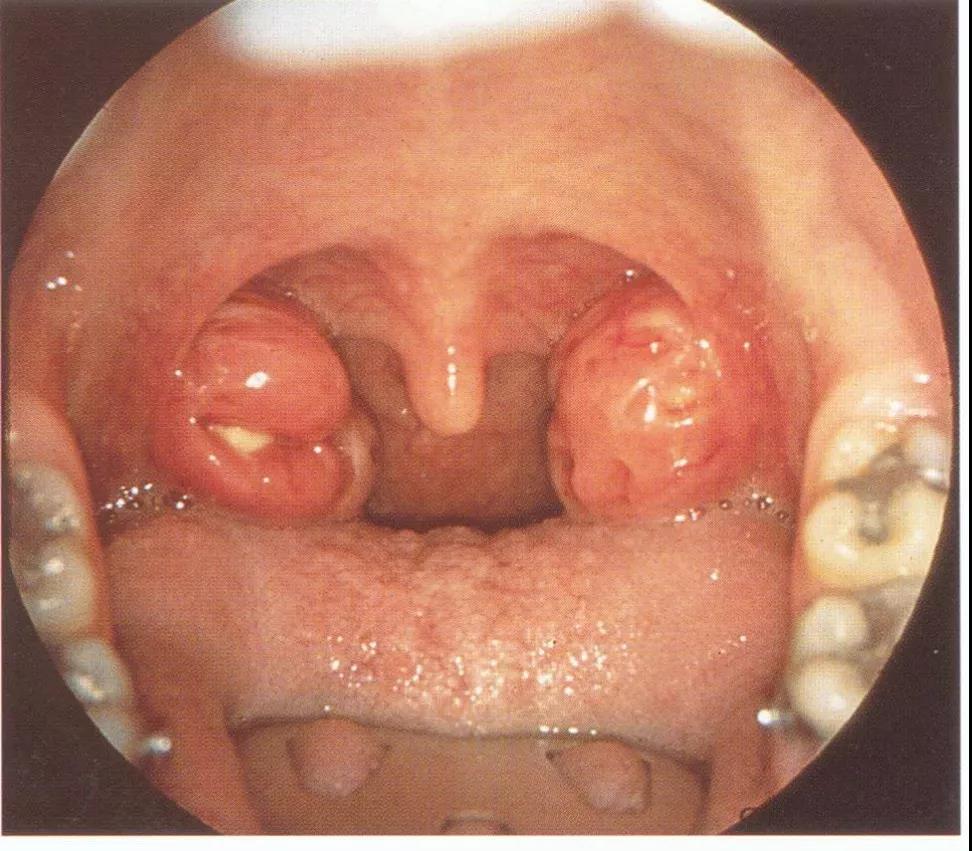

本病多单侧发病,两侧同时发病者极少。按其发生部位,临床上可分为前上型和后上型两种。前者脓肿位于扁桃体上极与舌腭弓之间,此型最常见;后者位于扁桃体与咽腭弓之间,较少见。

在扁桃体急性发炎3~4天后,发热仍持续不退或又加重,体温上升达39℃以上,咽痛加剧,吞咽时尤甚。常限于患侧,可放射至同侧耳部及牙齿。病情严重时患者头偏向患侧,不易转动(假性僵直)。讲话时似口中含物不清,张口受限,口内有多量粘稠唾液沿口角外流。同侧下颌角淋巴结常肿大。身体衰弱。

扁桃体脓肿:为扁桃体本身的脓肿,可在扁桃体内抽出脓液,患者扁桃体肿大,扁桃体上隐窝中可见脓液流出,患者多无张口困难。